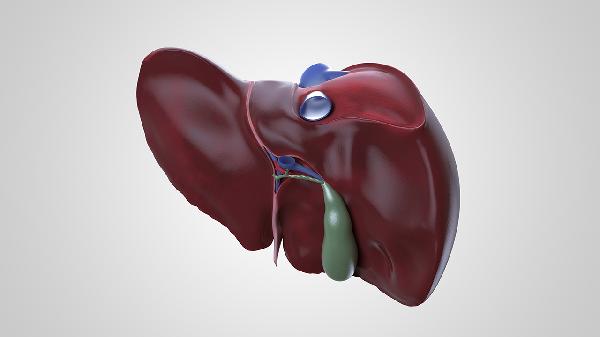

肝脏在必要时可以部分切除,但需严格评估剩余肝脏功能及手术适应症。肝脏切除手术主要用于治疗肝癌、肝血管瘤、肝内胆管结石等疾病,或作为肝移植的供体手术。

肝脏具有强大的再生能力,健康成年人切除70%以内的肝脏组织后,剩余肝脏可在数月内恢复至接近原体积。手术前需通过肝功能检查、影像学评估确保剩余肝脏体积足够维持机体代谢需求。对于肝硬化患者,安全切除范围通常不超过50%。常见术式包括左半肝切除、右半肝切除、肝段切除等,腹腔镜微创手术已广泛应用于临床。